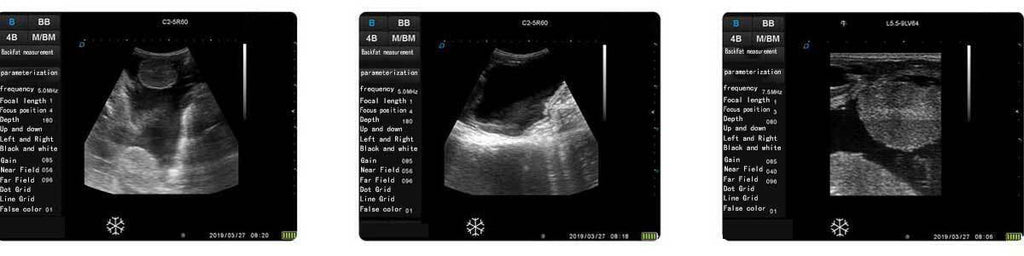

ECO-15Vet Bovine with Wireless Goggles, Convex Rectal Probe

Newest Model in Bovine sonography.

ECO15Vet veterinary ultrasound diagnostic machine is a newest research and development product by Dawei Veterinary Medical (Jiangsu) Co, Ltd. It adopts the new Acorn RISC Machine, compared with the traditional Microcontroller Unit, it has the characteristics of faster processing speed, stronger processing capacity, larger storage capacity, higher security performance, easier upgrade and maintenance, etc., which effectively brings greater convenience to users.